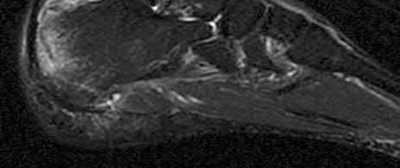

2. # A 35-year-old woman is involved in a head-on collision while driving. Initial radiographs are shown in Figures 8a and 8b. Injury to what vessel increases the risk for osteonecrosis of the injured bone?

5. Artery of the tarsal sinus Corrent answer: 4

The patient has a Hawkins type III talar neck fracture-dislocation with a risk of osteonecrosis ranging from 69% to 100%. Anatomic studies have shown that the artery of the tarsal canal supplies the lateral two thirds of the talar body.

The other vessels listed provide no significant contribution to the talus.